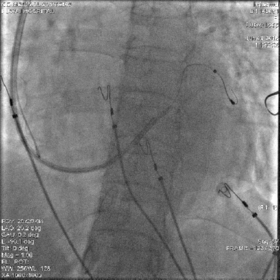

鞘中鞘经泥鳅导丝,通过瓣膜部位

鞘中鞘搭在靶静脉口

经鞘中鞘送左室导线进入侧静脉,张力大,左室导线前行困难

鞘中鞘前行支撑下仍无法进入

将鞘中鞘被再次送到靶静脉口支撑,由于分支太细,左室导线仍无法深入

调整左室导线,进入另一位置较高的分支

再次尝试PTCA导丝进入较高分支,左室导线顺利进入

放置心房心室导线